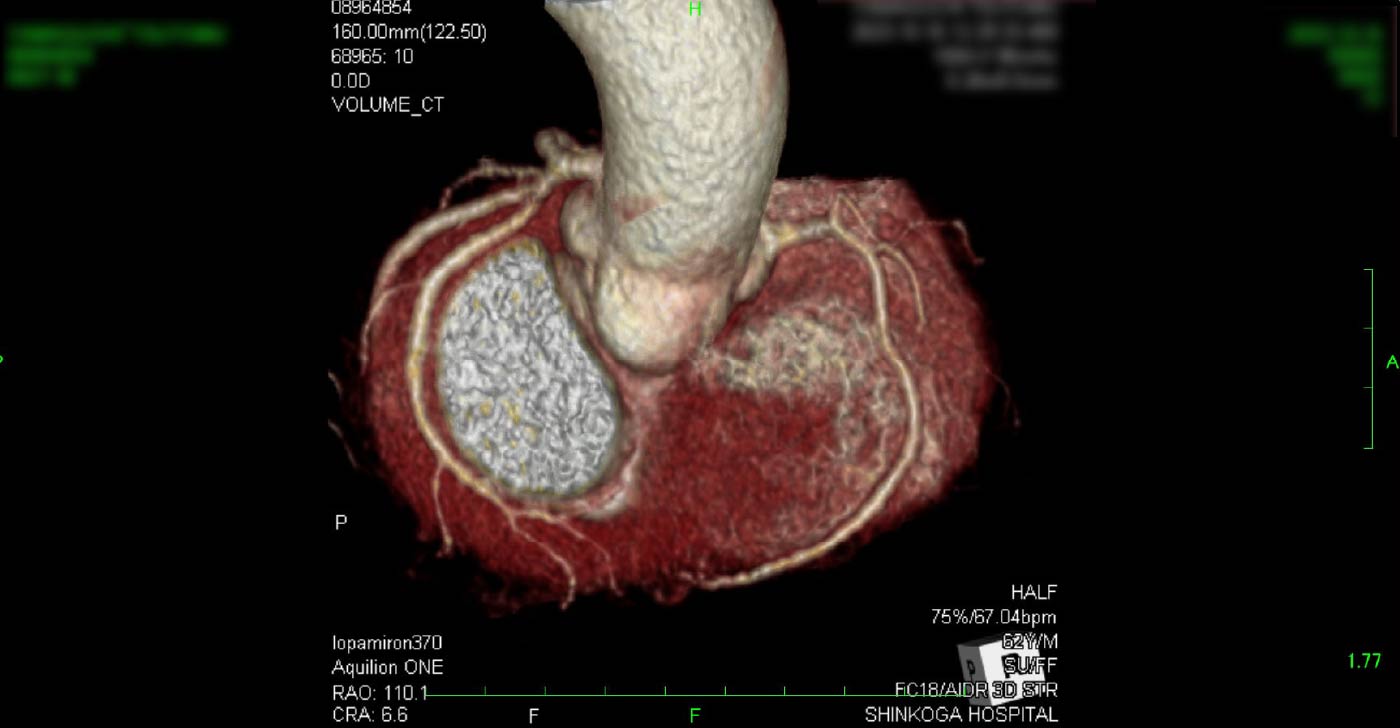

進行期 造影心臓CT 重症心筋虚血症例

冠動脈CT

狭心症を安全に診断あるいは除外する!

連携施設の新古賀病院で速やかに実行可能です。

冠動脈CT 冠動脈CT 冠動脈CT 冠動脈CT 冠動脈CT 冠動脈CT 冠動脈CT 冠動脈CT 冠動脈CT 冠動脈CT 冠動脈CT 冠動脈CT 冠動脈CT 冠動脈CT